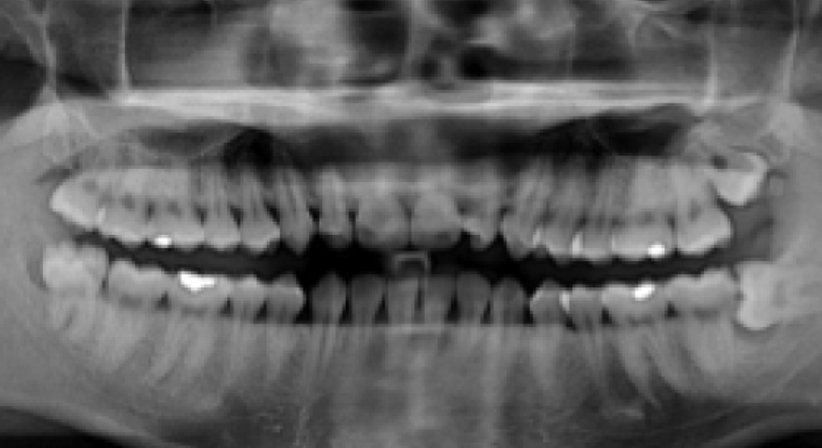

Der Weisheitszahn ist von der Mitte aus gezählt der achte Zahn im menschlichen Gebiss. Normalerweise hat ein Mensch vier Weisheitszähne, in jedem Gebissquadranten einen. Sie brechen meist erst im Erwachsenenalter, teilweise gar nicht durch. Die Anzahl der Wurzeln ist unterschiedlich. Sie können miteinander verwachsen oder hakenförmig gebogen sein, so dass eine notwendige Extraktion der Zähne erschwert ist. In seltenen Fällen wachsen hinter den Weisheitszähnen noch überzählige Weisheitszähne, so genannte Distomolaren, auch Neuner genannt.

Das Missverhältnis zwischen Kiefergröße und Zahnanzahl führt am Kieferwinkel, dem Übergang vom horizontalen zum aufsteigenden Ast des Unterkiefers dazu, dass sie häufig keinen ausreichenden Platz mehr finden und vollständig retiniert bleiben oder nur unvollständig durchbrechen (Teilretention). Vollständig retinierte Zähne bleiben normalerweise symptomlos, teilretinierte führen hingegen oft zu Entzündungen (siehe: Dentitio diffiziles), die sich zu Abszessen entwickeln können. Ursache für eine solche Entzündung ist die Bildung einer kapuzenförmigen Zahnfleischtasche, die nur schwer oder gar nicht gereinigt werden kann. Bakterien können sich in dieser Tasche mit Hilfe von sich zersetzenden Speiseresten schnell vermehren. Deshalb müssen Weisheitszähne sehr oft entfernt werden.